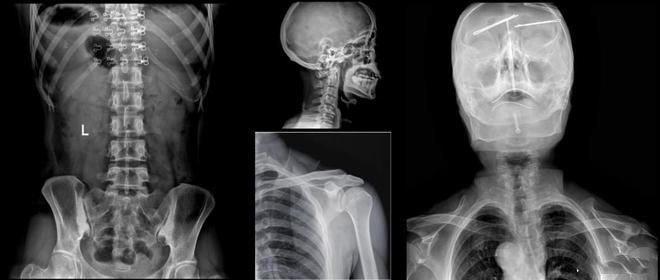

进入21世纪,数字化放射科建设已逐渐成为放射界、医院发展的重点之一。放射科作为日常纷繁医学影像诊断业务的承接科室,最需要的就是在短时间内可以完成高品质成像的高效数字化X线成像系统。浙江大学医学院附属邵逸夫医院放射科引进美诺瓦Staray双立柱智能DR,可用于颈椎、胸部、腹部等站立和头颅、四肢、脊柱等卧位的数字化X摄影,自2020年4月启动至今设备已超24个月,整机保持高开机率稳定运行,有效地提高了放射科的诊断水平和速度,缓解患者的就医压力,提升就诊体验。

美诺瓦Staray双立柱智能DR在2021年被中国医学装备协会评为“优秀国产医疗设备”搭载了非晶硅碘化铯超清平板探测器、分体式大热容X线球管、自主研发50KW大功率高压发生器以及Staray图像算法工作站,在患者登记、摄影条件选择、患者摆位、图形采集处理乃至PACS网络传输等整个检查流程上均采用了新流程技术,操作简单,特别是智能机架控制、智能多维联动功能、智能防碰撞、智能胸高识别等功能,一体化电动控制摆位,让医生操作更加便捷,有效解决了普放常规检查项目患者流通量大,高峰时间拥挤的问题。

美诺瓦Staray双立柱智能DR采用自研核心数字医学影像链技术,成像速度快,放射技师即刻在屏幕上观察到高清图像,病灶一览无余,辅助医生进行更加精准的诊断,AEC自动曝光控制,让拍摄剂量控制更加轻松,省时省力。